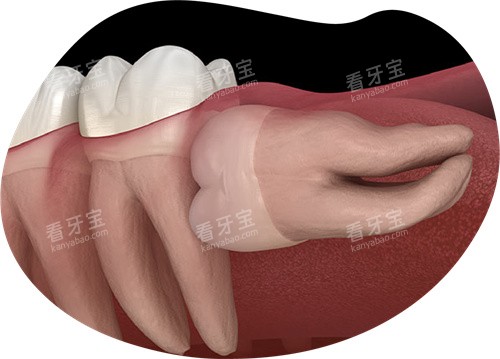

阻生智齿压迫邻牙导致牙根吸收。

复杂阻生齿(未萌出、靠近神经管):建议综合医院口腔颌面外科。